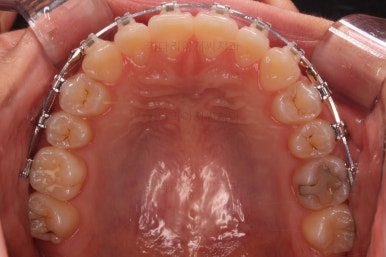

장치를 부착한 직후츼 사진입니다.

장치를 따라 걸려있는 철사의 형태를 보면 생각보다 많이 틀어져 있었구나 하고 느껴지게 되실거에요.

이번에 부착한 장치는 엠파워 클리어라고 하는 자가결찰 세라믹장치 입니다.(아마 이 장치 나올 때마다 설명드리는 것 같은데) 매우 유명한 클리피씨라고 하는 장치와 같은 컨셉의 장치입니다.

단지 제조 회사가 다를 뿐이죠.

(엠파워는 미국장치, 클리피씨는 일본장치)

술자의 선호도에 따라 장치가 선택되는데 클리피씨 보다는 부산치아교정잘하는곳인 키다리아저씨치과에서는 엠파워를 약간은 더 선호하고 있습니다.